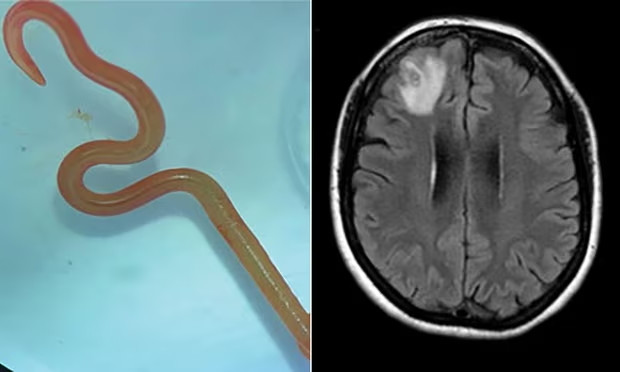

Neurohirurg, dr. Hari Priya Bandi, izvukao je 8 cm dugog parazitskog okruglog crva iz svog pacijenta, što ju je navelo da se obrati Senanayakeu i drugim bolničkim kolegama za savjet o tome šta dalje.

MRI skeniranje njenog mozga otkrilo je abnormalnosti koje su zahtijevale operaciju. “Ali neurohirurg sigurno nije ušao tamo misleći da će pronaći crva koji se migolji”, rekao je Senanayake. “Neurohirurzi se redovno bave infekcijama u mozgu, ali ovo je bio nalaz koji se dešava jednom u karijeri. Niko nije očekivao da će to pronaći.”

“Canberra je malo mjesto, pa smo crva, koji je još bio živ, poslali pravo u laboratoriju naučnika CSIRO-a koji ima vrlo veliko iskustvo s parazitima”, rekao je Senanayake. “On ga je samo pogledao i rekao: ‘O moj Bože, ovo je Ophidascaris Robertsi’.”

Ophidascaris robertsi je okrugli crv koji se obično nalazi u pitonima. Pacijent u bolnici u Canberri označava prvi slučaj u svijetu da je parazit pronađen kod ljudi.